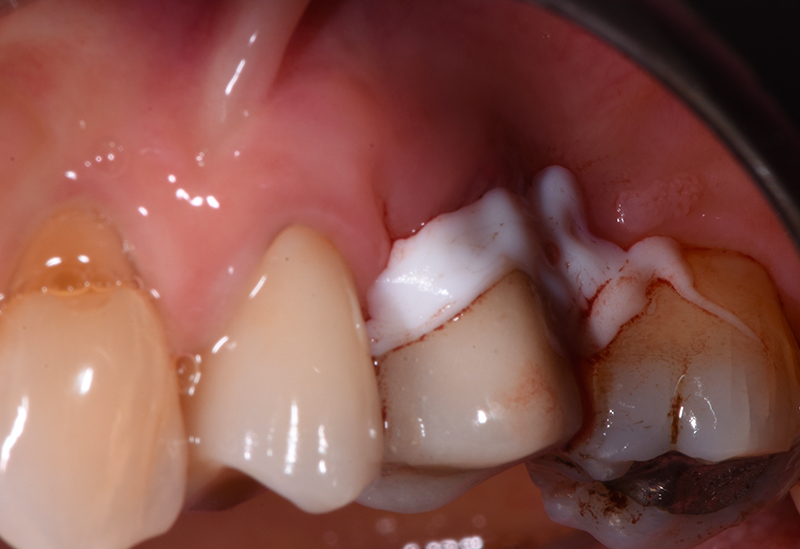

A 6 mesi dal baseline (t4) si esegue rivalutazione. La paziente viene sottoposta a esame radiografico e documentazione fotografica (Figs. 8-9). All’esame visivo i tessuti molli perimplantari si presentano in buono stato, in termini di colore e consistenza.

Fig. 8 - Rivalutazione fotografica a sei mesi in cui è possibile apprezzare la riorganizzazione dell'architettura gengivale peri-implantare con aumento dei volumi del tessuto nelle aree prossimali alla fixture, accentuata la contrazione nel punto vestibolare.